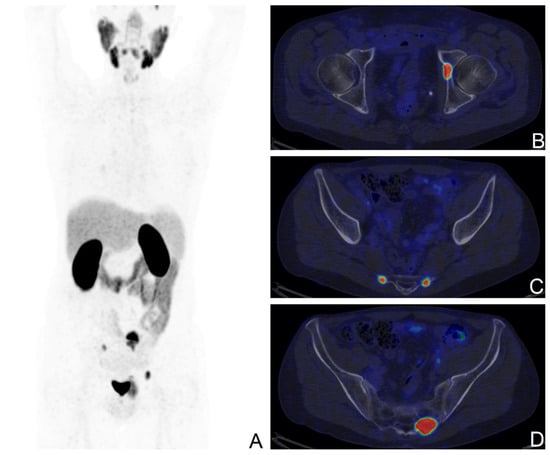

[68Ga]Ga-PSMA-11 PET was positive in 39/80 patients (median PSA: 0.43 ng/mL, range: 0.13–4.66) and negative in 41/80 (median PSA: 0.3 ng/mL, range: 0.01–5.22). On a regional basis, [68Ga]Ga-PSMA-11 uptake was observed in correspondence of the prostatic fossa in 6/39 patients (15%), of lymph nodes in 27/39 patients (69%), of bone in 12/39 patients (31%), and in the lungs in 1/39 patients. Among the 27 patients with lymph-nodal [68Ga]Ga-PSMA-11 uptake, 20/27 showed involvement of regional lymph nodes only, 4/27 solely non-regional lymph nodes, and in 3/27 [68Ga]Ga-PSMA-11 uptake was present in both regional and non-regional lymph nodes. Five patients with PSA < 0.2 ng/mL showed pathological findings at PET, all of them presenting pT ≥ 3a (Figure 1 and Figure 2).

Figure 2. [68Ga]Ga-PSMA-11 PET/CT scan of a BCR patient with the ISUP score of 5, pT3a after RP; PSA levels at the time of the scan: 1.43 ng/mL; Maximum Intensity Projection image (A), fused axial PET/CT views showing secondary bone lesions at the left acetabulum (B), and at the sacrum bilaterally (C,D).